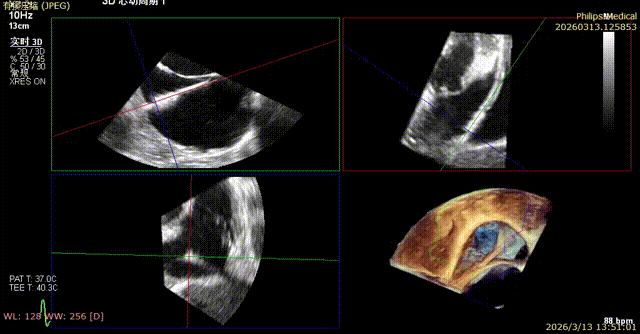

Comparison of Regurgitation Before and After Surgery

Baseline preoperative regurgitation

Comparison of Tricuspid Annular Area After Annuloplasty

Preoperative tricuspid annular area: 15.6 cm²

Following annuloplasty, leaflet coaptation was improved compared with the preoperative state, and regurgitation was reduced from severe to trivial.